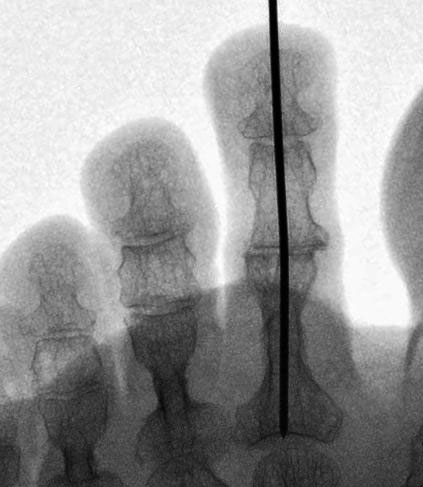

Eine relativ neue Entwicklung stellt die Verwendung spezieller intramedullärer Implantate dar. Mittlerweile sind eine Vielzahl unterschiedliche Systeme auf dem Markt. Ein wichtiges Unterscheidungsmerkmale ist die Art der Verankerung im Knochen. Dabei kann zwischen Systemen die eingeschraubt werden und Press-fit-Systemen, teilweise unter Verwendung von Formgedächtnislegierungen, unterschieden werden. Zudem wird zwischen einteiligen und zweiteiligen Systemen unterschieden. Bei zweiteiligen Systemen werden beide Komponenten getrennt implantiert und danach ineinander gesteckt.

• Eine Röntgenkontrolle wird 6 Wochen postoperativ durchgeführt (Fuß belastet in zwei Ebenen). Besonders geachtet wird auf eine knöcherne Konsolidierung der Arthrodese und auf die Lage eines gegebenenfalls verwendeten intramedullären Implantats.

Bezüglich der Verwendung von intramedullären Implantaten liegen nur wenige Berichte in der Literatur vor. Ellington et al. beschreiben eine knöcherne Fusionsrate von 60% beim Gebrauch des Stay-fuse Implantats (Tornier, Minneapolis, Minn., USA) bei insgesamt 38 korrigierten Zehen. Eine persistierende Fehlstellung in sagittaler oder coronaler Ebene trat in 18% der Fälle auf. Ein Revisionseingriff war bei drei Patienten erforderlich. Die Autoren schlussfolgern,  dass das Implantat die Korrektur ausreichend stabilisiert, obwohl die Fusionsrate vergleichbar ist mit der bei der Verwendung eines K-Drahtes zur Stabilisierung 8.  Roukis berichtet über klinische und radiologische Ergebnisse nach Benutzung des Smart Toe Implantates zu Arthrodese des PIP-Gelenks (Stryker, Kalamazoo, Mich., USA) Dabei wurde eine Fusionsrate von 93% sowie eine Malunion-Rate von 7% bei 30 Zehenkorrekturen ermittelt 9. In einer anderen retrospektiven, vergleichenden Studie von Angirasa, werden die Ergebnisse der PIP-Arthrodese unter Verwendung von K-Drähten mit dem Gerbrauch von SmartToe® Implantates (Stryker, Kalamazoo, Mich., USA) verglichen. In dieser Studie ergeben sich Vorteile für die Verwendung des intramedullären Implantates in Bezug auf Schmerzsymptomatik, Komplikationen, Rate der erreichten Arthrodese, und Zeitperiode bis zur Wiederaufnahme der Arbeit 10.